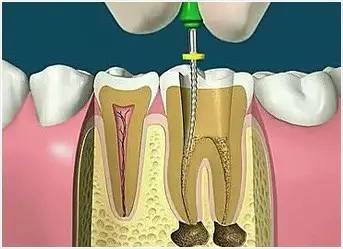

4、根管预备

根管清理成形的目的是去净根管壁上的感染物,通过根管器械的切削作用去除感染的牙本质并清理根管壁细菌以利于根管充填。

5、根管冲洗、消毒

根管冲洗的目的是清除微生物、冲掉残渣,润滑根管器械和溶解有机残渣。然后,再进行根管消毒,使根管内达到无菌状态。